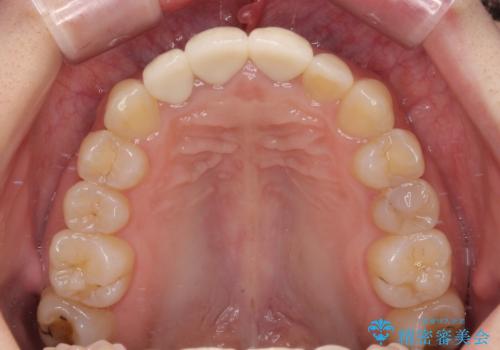

金属を除去したことで、周りと調和した自然な色合いとなり、クラウンの際の位置も歯肉に少し入り込む位置となっているためまるで本物の歯のような仕上がりとなりました。